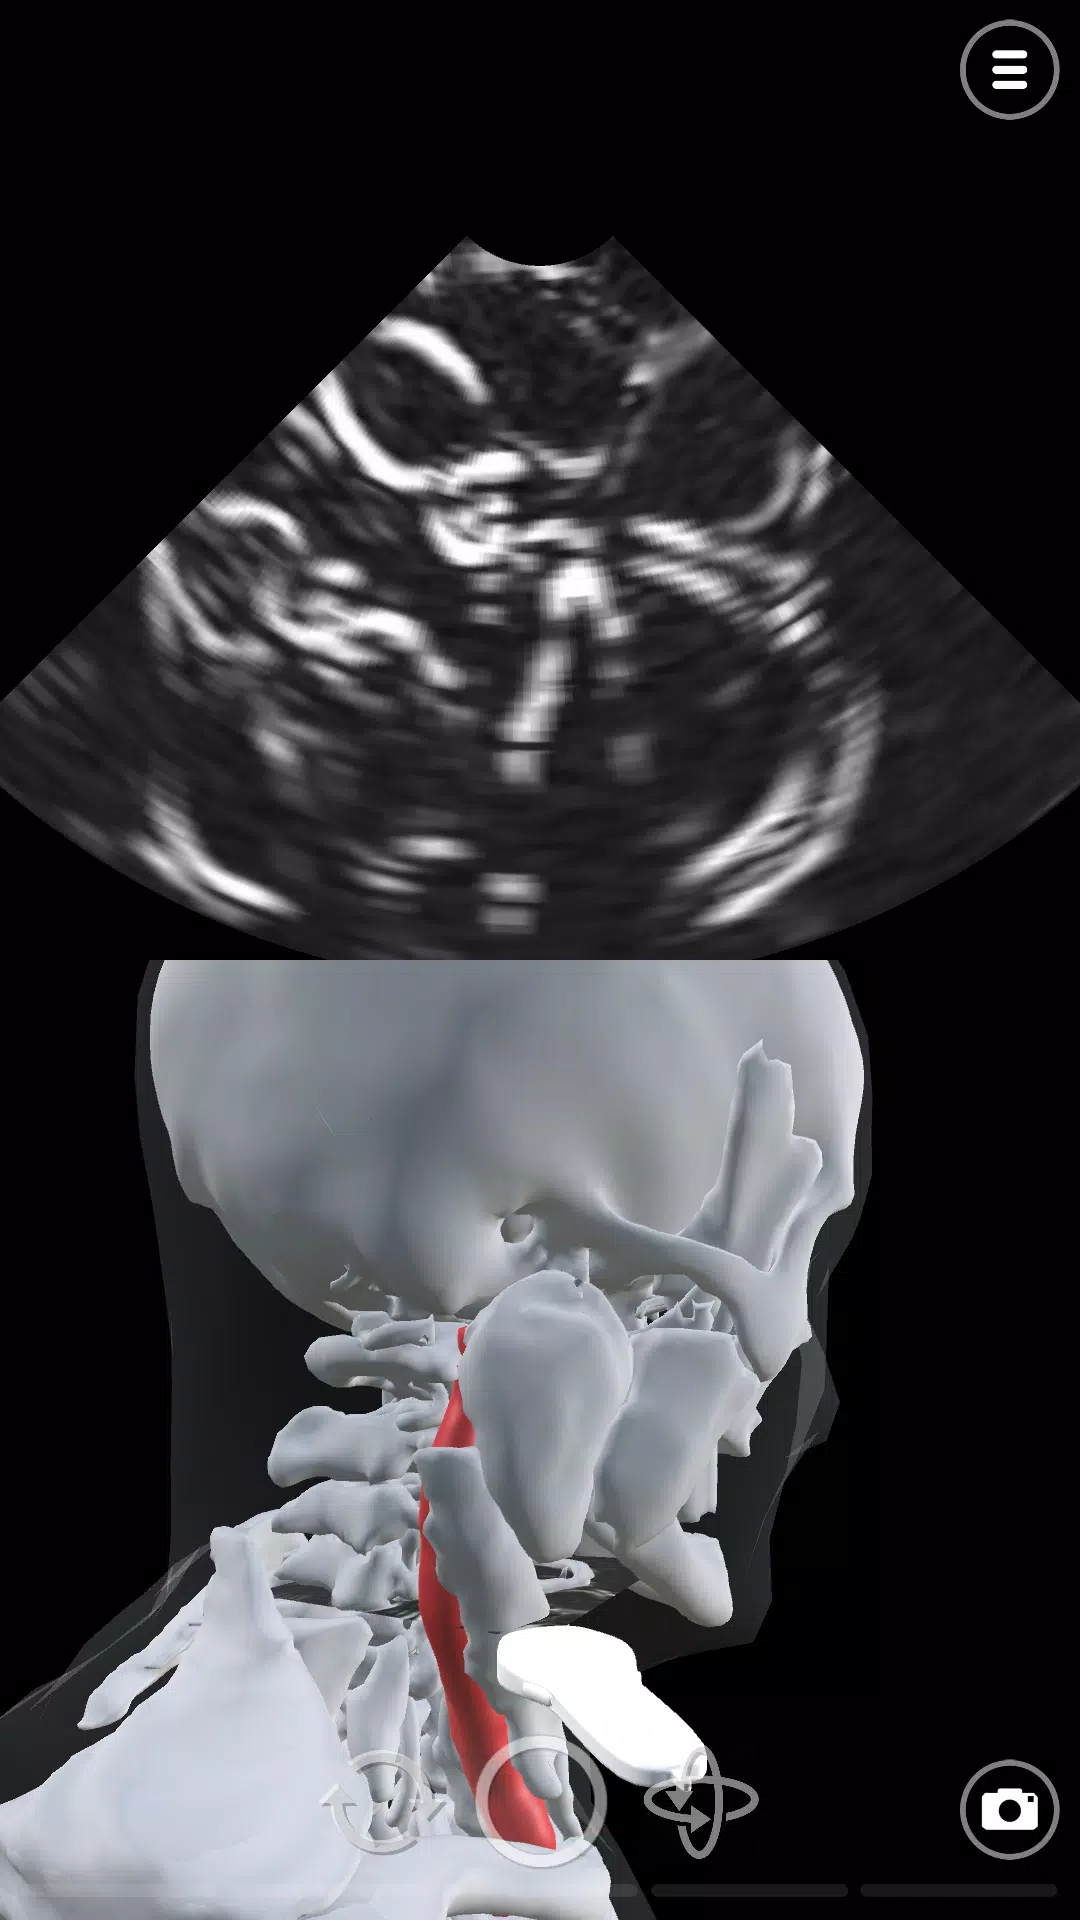

在超声模拟器中学习超声波或超声波扫描技术。 Deepscope超声学习模块由医生和超声医师创建。模块包括: - 基本超声或超声波探头运动 - 与超声扫描检查相关的解剖学 - 进行主动脉超声检查或超声检查的技术 - 进行超声心动图或回声的技术超声模拟器使用先进的计算机图形技术模拟声波。超声波图是作为这些模拟的结果而创建的。该应用程序旨在学习超声波检查或超声波。它可用于急诊医学(ER)超声,手术(术前)超声,骨科超声扫描,风湿病超声检查,血管超声检查,眼科超声和麻醉超声(麻醉学)。对于心脏病学,我们有超声心动图和回声模拟。Deepscope chāoshēng xuéxí mókuài yóu yīshēng hé chāoshēng yīshī chuàngjiàn.Mókuài bāokuò: - Jīběn chāoshēng huò chāoshēngbō tàntóu yùndòng - yǔ chāoshēng sǎomiáo jiǎnchá xiāngguān de jiěpōu xué - jìnxíng zhǔ dòngmài chāoshēng jiǎnchá huò chāoshēng jiǎnchá de jìshù - jìnxíng chāoshēng xīndòng tú huò huíshēng de jìshùchāoshēng mónǐ qì shǐyòng xiānjìn de jìsuànjī túxíng jìshù mónǐ shēngbō. Chāoshēngbō tú shì zuòwéi zhèxiē mónǐ de jiéguǒ ér chuàngjiàn de.Gāi yìngyòng chéngxù zhǐ zài xuéxí chāoshēngbō jiǎnchá huò chāoshēngbō. Tā kěyòng yú jízhěn yīxué (ER) chāoshēng, shǒushù (shù qián) chāoshēng, gǔkē chāoshēng sǎomiáo, fēngshī bìng chāoshēng jiǎnchá, xiěguǎn chāoshēng jiǎnchá, yǎnkē chāoshēng hé mázuì chāoshēng (mázuì xué). Duìyú xīnzàng bìng xué, wǒmen yǒu chāoshēng xīndòng tú hé huíshēng mónǐ. 最新版本2.0更新日志 Last updated on 2023年10月24日 New ModulesNew User Interface